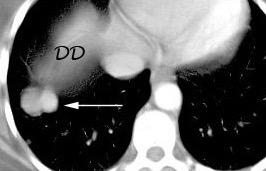

Visualización del diafragma, incluso en la parte central, debido al neumomediastino

Neumonía intersticial usual. Neumomediastino. Enfisema subcutáneo

Zylak CM et al. Pneumomediastinum Revisited. Radiographics 2000

El aire en la cavidad pleural, neumotórax, queda en ocasiones atrapado en la base pulmonar, siendo difícil el diagnóstico diferencial con neumomediastino.